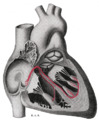

Figure 1 shows the conduction system of the heart. The SA node is labelled 1.

The sinoatrial node (also known as the sinuatrial node, SA node or sinus node) is a group of cells located in the wall of the right atrium of the heart.[1] These cells have the ability to spontaneously produce an electrical impulse (action potential; see below for more details), that travels through the heart via the electrical conduction system (see figure 1) causing it to contract. In a healthy heart, the SA node continuously produces action potential, setting the rhythm of the heart and so is known as the heart's natural pacemaker. The rate of action potential production (and therefore the heart rate) is influenced by nerves that supply it.[2]